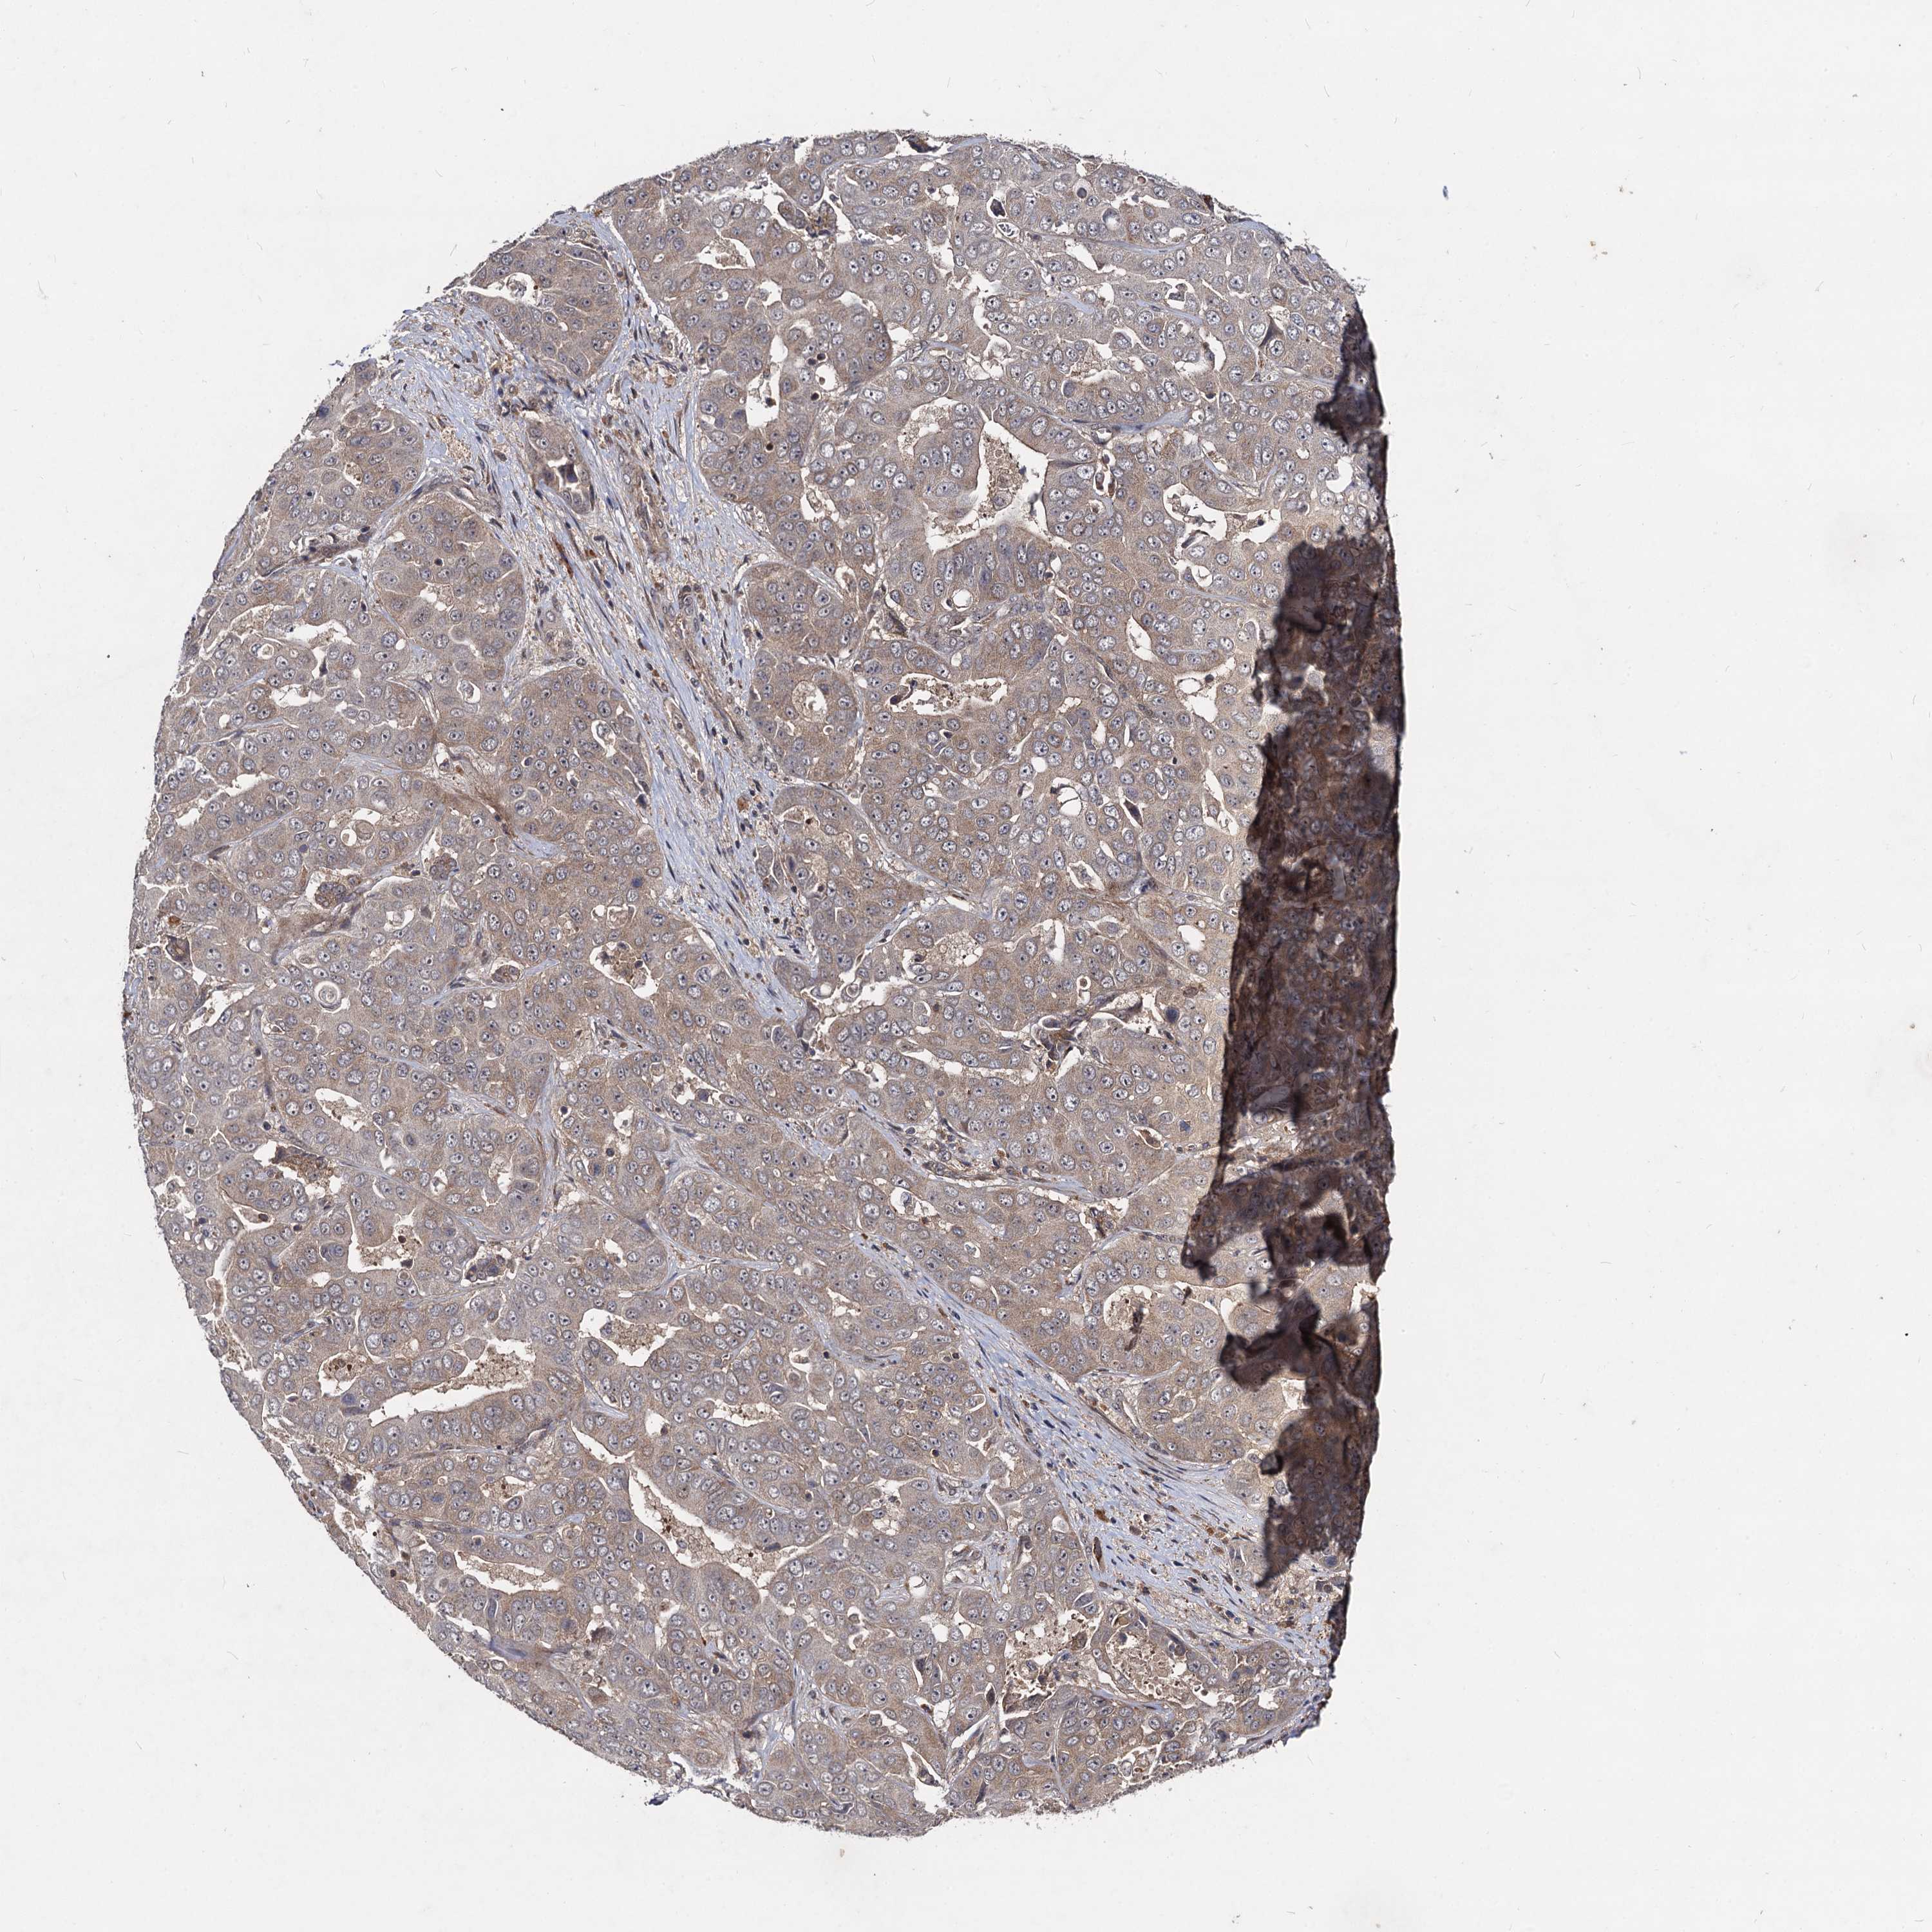

LIVER CANCER - Protein expressioni

A mouse-over function shows sample information and annotation data. Click on an image to view it in a full screen mode. Samples can be filtered based on level of antibody staining by selecting one or several of the following categories: high, medium, low and not detected. The assay and annotation is described here.

Note that samples used for immunohistochemistry by the Human Protein Atlas do not correspond to samples in the TCGA dataset.

Antibody stainingi

Antibody staining in the annotated cell types in the current human tissue is reported as not detected, low, medium, or high, based on conventional immunohistochemistry profiling in selected tissues. This score is based on the combination of the staining intensity and fraction of stained cells.

Each image is clickable and will lead to virtual microscopy that enables deeper exploration of all samples and also displays staining intensity scores, fraction scores and subcellular localization as well as patient and tissue information for each sample.

Antibody HPA041507

Antibody HPA041599

Cholangiocarcinoma

Carcinoma, Hepatocellular, NOS